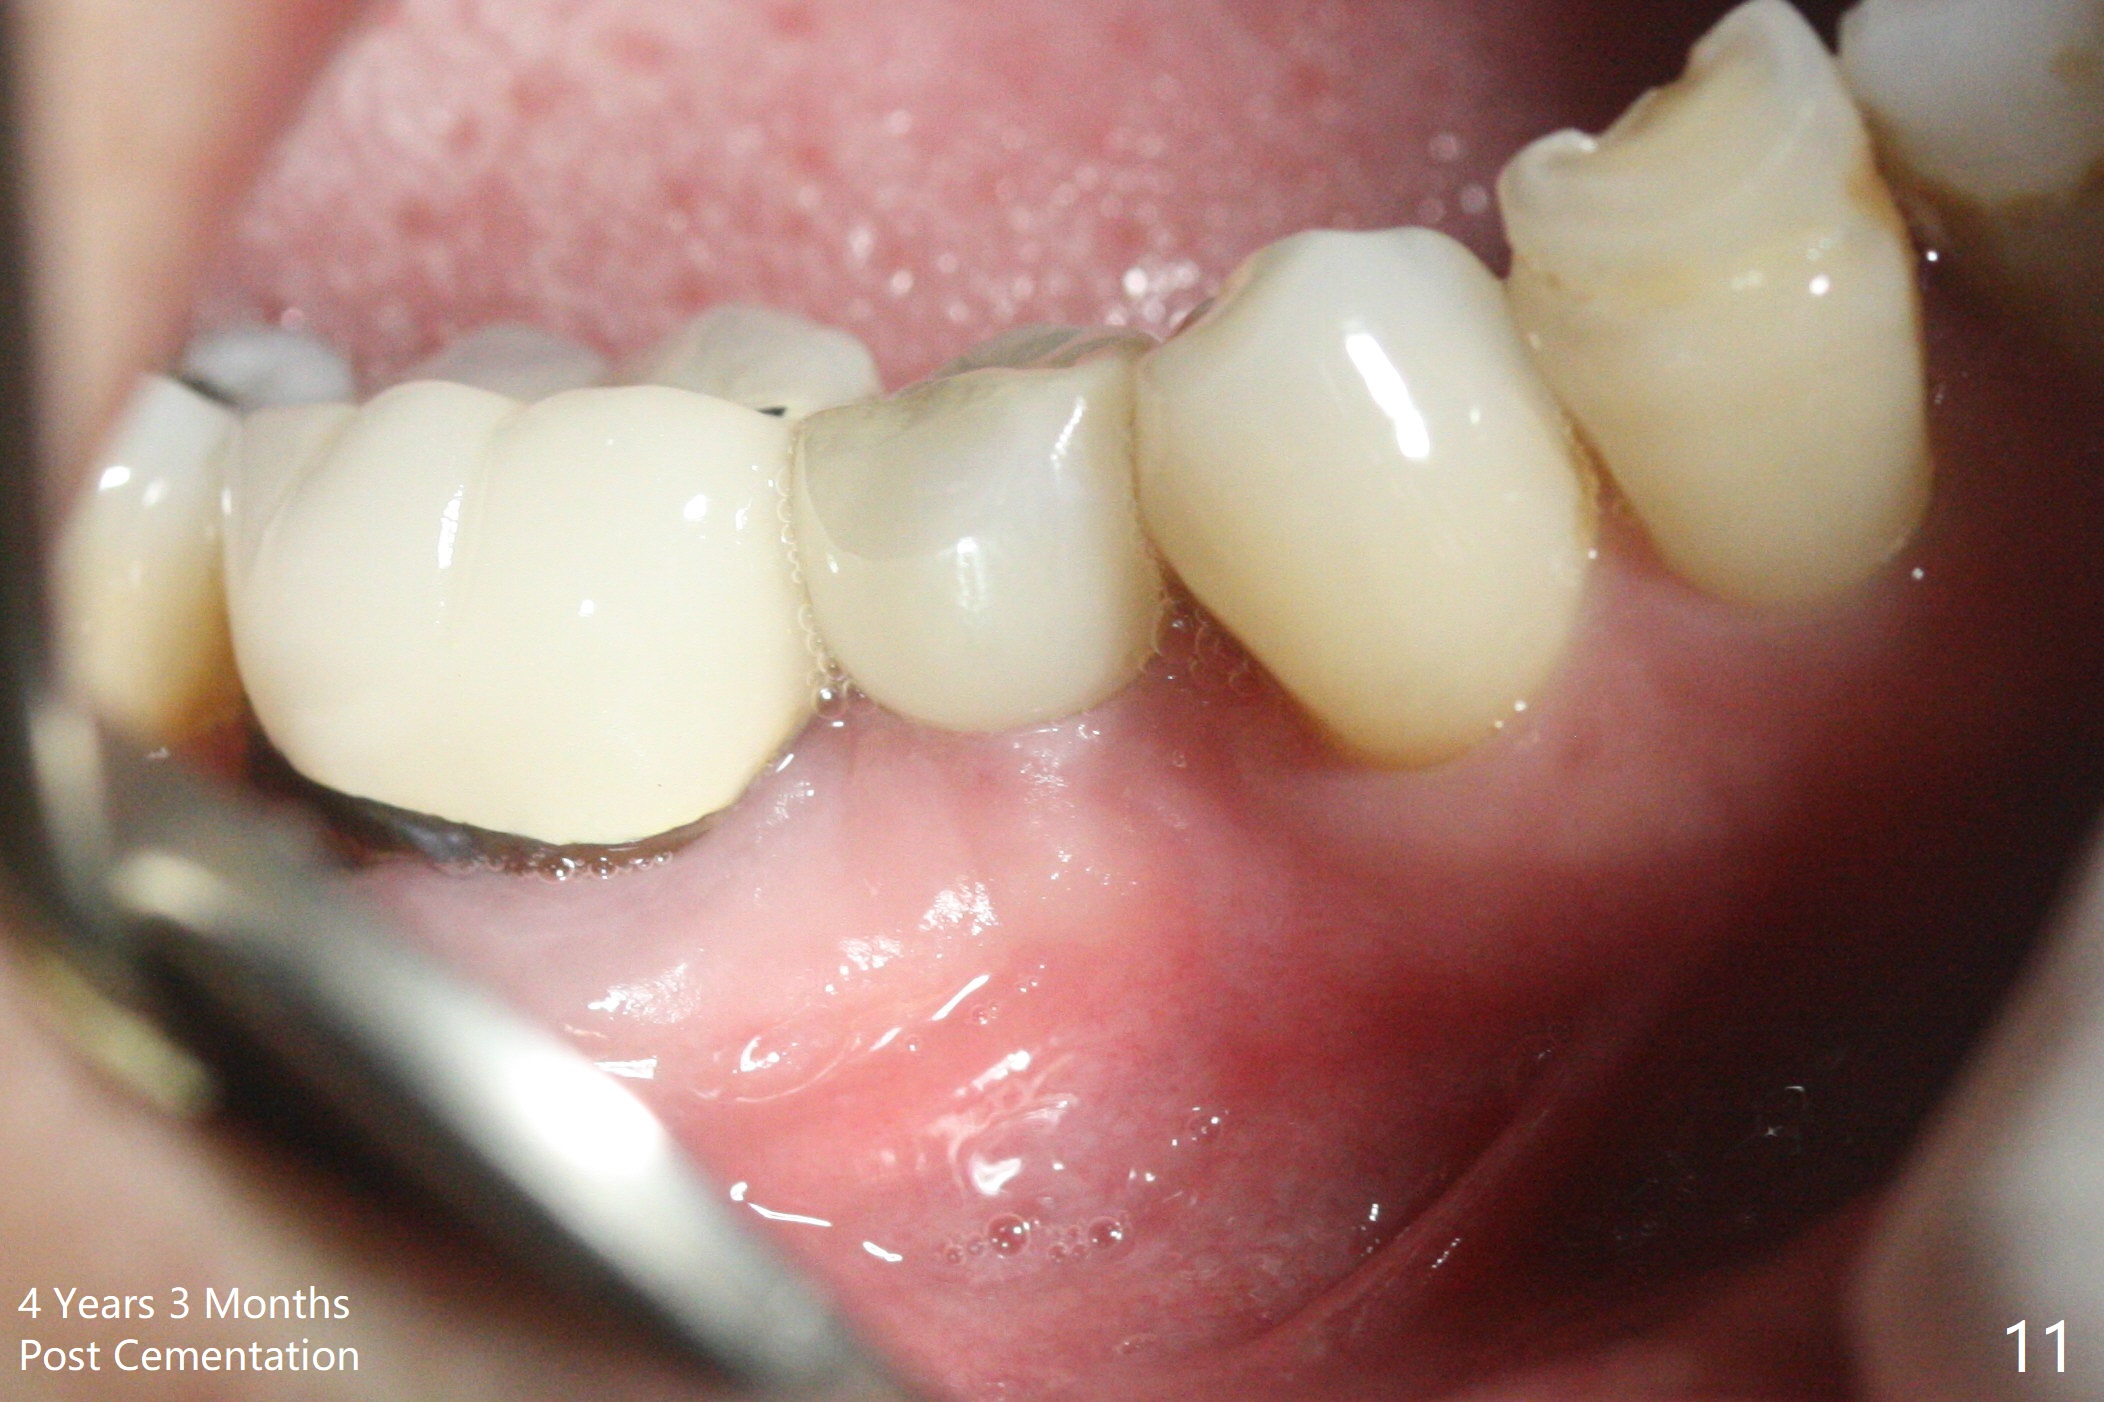

Preop photo shows the distal inclination of the tooth #28 (Fig.1).  The distal surface of the latter is reduced before incision for implant placement at #29 (Fig.2).  The buccolingual width is approximately 4 mm, as compared to 3 mm implant positioner (Fig.3).  After 1.2x10 mm osteotomy (Fig.5), the mesiodistal cortical bone is removed with a small high-speed fissural bur (Fig.4).  When a 2.5x12(2) mm 1-piece implant is placed (Fig.6), there is no buccal (Fig.7) or lingual plate perforation.  There is no postop paresthesia.  There is mild bone loss distal 4 months postop (Fig.8 *).  Take photos before and after permanent crown cementation to show increase in ridge width after bone graft and improvement in gingival health after provisional modification.  Take PA and/or BW post cementation to show that the distal bone resorption (Fig.8 *) is partially due to angulation.  No continuous bone loss 15 months post cementation (Fig.9).  There is mild bone resorption mesially 2 years 3 months post cementation (Fig.10).  The soft and hard tissues remain healthy 4 years 3 months post cementation (Fig.11,12).